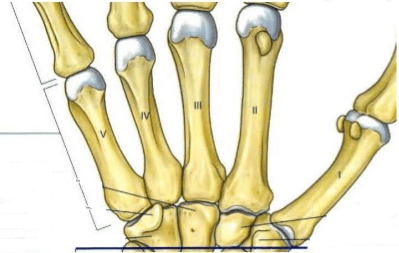

Estos huesos forman propiamente la mano

Metacarpos

Escribe en tu libreta los nombres correctos de los huesos de la muñeca (no debe faltar alguno)

Trapecio, trapezoide, grande, ganchoso, pisiforme, piramidal, semilunar, escafoides.